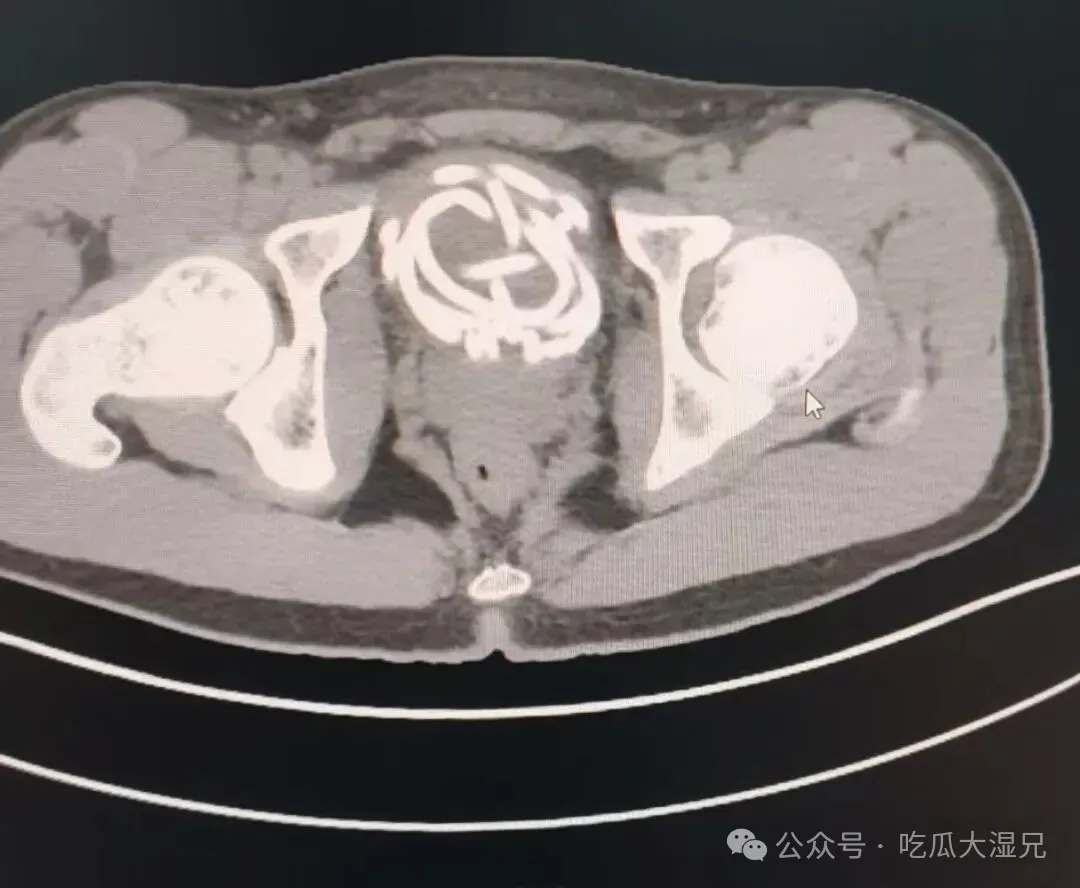

据了解,这名男生因一时好奇,将橡胶跳绳插入尿道,无法取出,随后出现剧烈疼痛、排尿困难等症状。医生立即为患者进行相关检查。检查结果显示,跳绳已经在膀胱内打结盘曲,由于滞留时间较长,患者尿道已出现严重感染并形成脓胎,如果不及时手术,可能引发更加严重的并发症。

在手术过程中,医生看到患者尿道黏膜因为异物刺激已经布满脓苔,跳绳相互缠绕,形成难以解开的死结。为最大程度减少创伤,医生团队采用腹腔镜下膀胱切开异物取出术,通过微小穿刺切口,在腔镜直视下将打结跳绳剪断后分段取出。手术创伤小、出血少、恢复快,最大限度保护了患者泌尿功能。术后,医院联合儿外科进行抗感染等对症治疗,目前患者病情平稳。